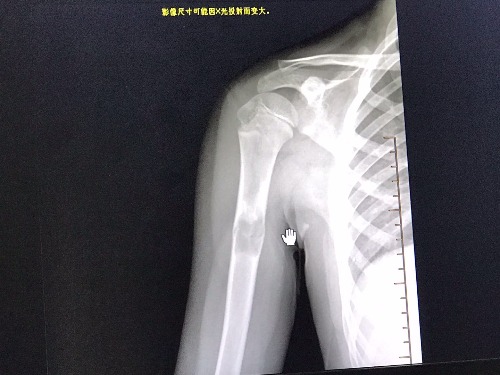

PED5416:肱骨低密度影,求大咖给把把!

男12岁 两日前外伤拍片。之前无任何不适。

右肱骨中上1/3交界段可见囊状骨质破坏且见骨片陷落征。考虑:右肱骨骨囊肿伴病理性骨折。

病灶内有硬化,有分隔,似有磨玻璃影,考虑骨纤。

右肱骨中上段骨囊肿并病理性骨折。

动脉瘤样骨囊肿?